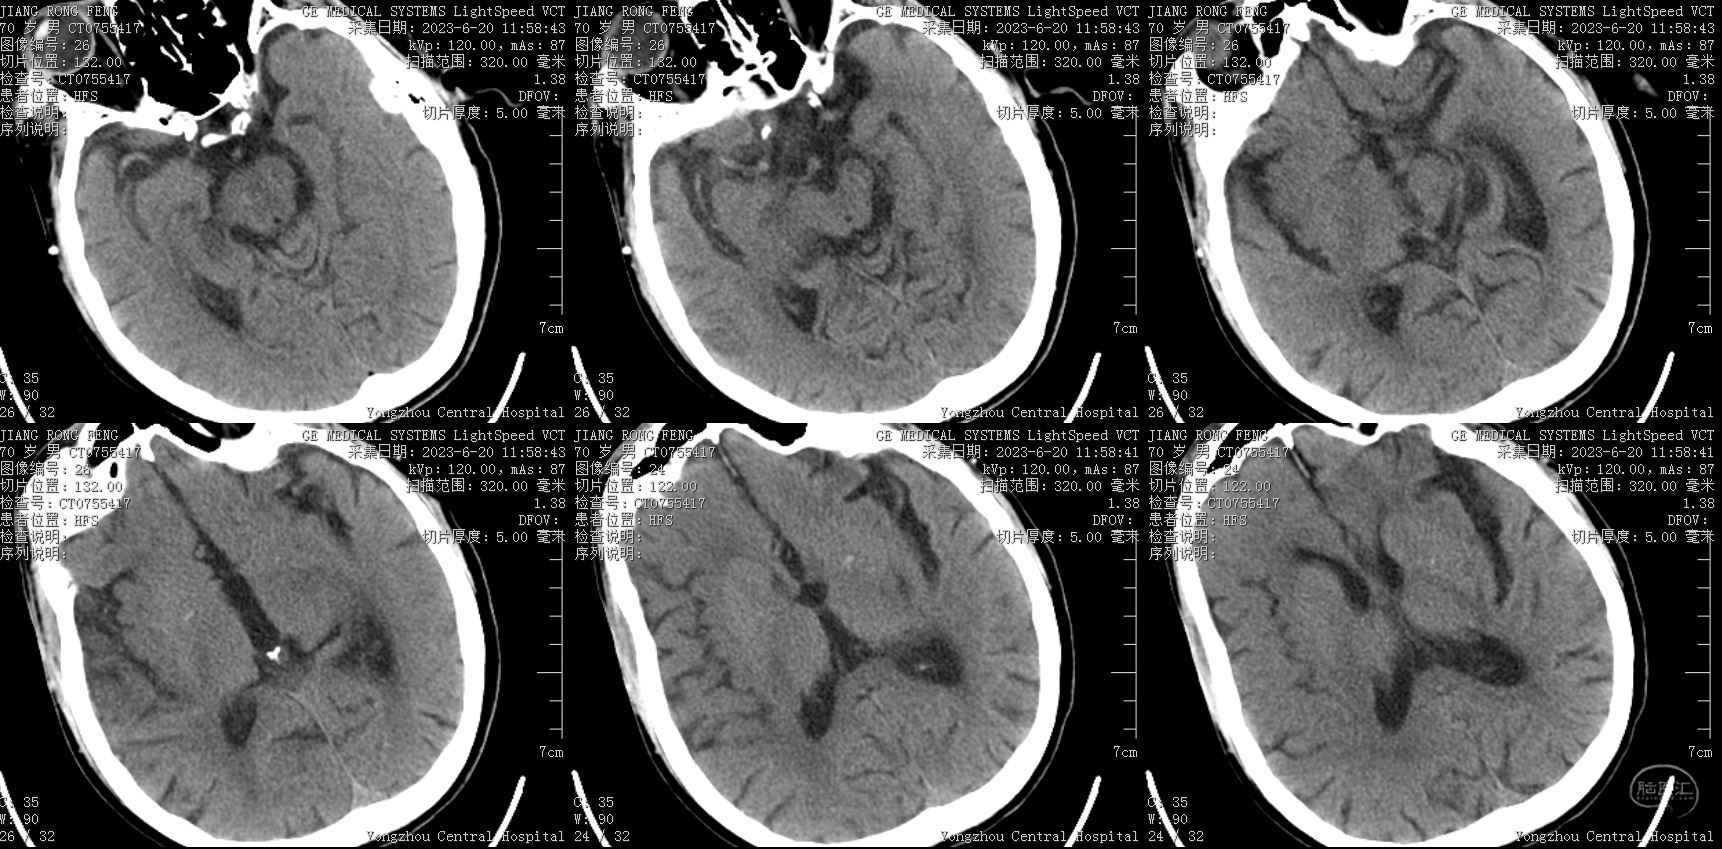

辅助检查:2023-6-20我院头颅CT及CTA示:右侧颈内动脉C1、C2段栓塞,右侧大脑中动脉M1、M2段栓塞,远端分支减少。右侧椎动脉V1段起始处狭窄;左侧C1段起始处狭窄。右侧额颞顶叶可疑稍低密度影。

入院急诊头颅CT,右侧大脑中动脉走形可见疑似高密度征。

入院急诊头颅及颈部血管CTA,提示多根血管病变,右侧责任血管串联病变可能。